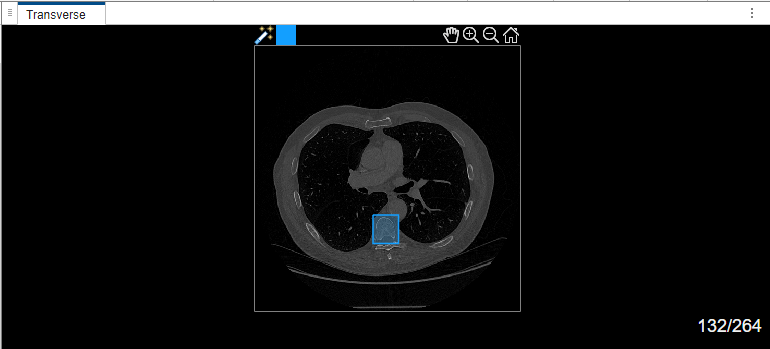

Select label Type1. Draw a bounding box around the object to segment in the transverse plane of the volume.

If you are segmenting objects in a medical image or a 2-D slice image of a medical volume for the first time in the app, and if you are not using a GPU, the MedSAM algorithm takes some time to extract embeddings for the image. In this case, the app displays the Running MedSAM model dialog box.

Once the MedSAM algorithm extracts the embeddings of the image, you can adjust the bounding box.

The MedSAM algorithm segments the object in the bounding box and labels it.